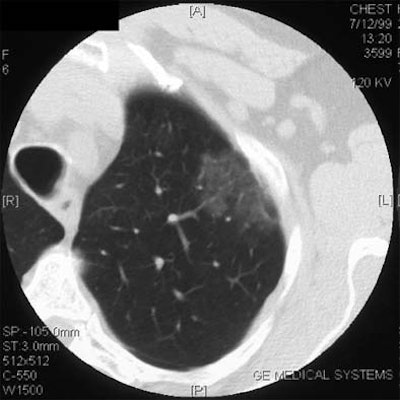

| Non-solid nodule. |

Japanese researchers have found distinct prognostic differences among nodule types in thin-section CT, Yankelevitz said. In a Radiology study, for example, Aoki and colleagues found that adenocarcinomas smaller than 2 cm with a ground-glass component of more than 50% were highly unlikely to have lymph node metastases or vessel invasion. The group concluded that thin-section CT may be a helpful tool in determining the eligibility of patients for resection (Radiology, Sept. 2001, Vol. 220:3, pp. 803-809).